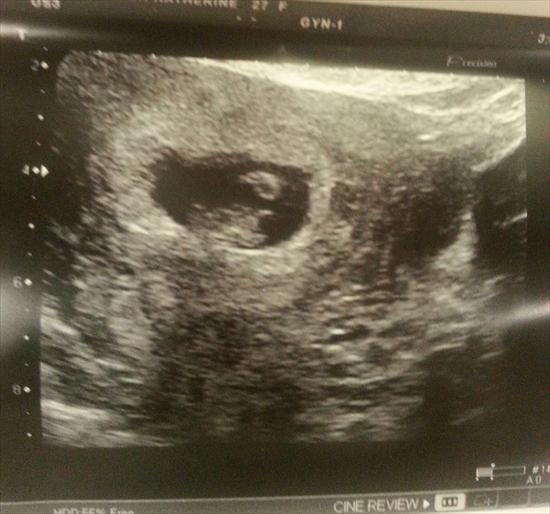

this is a comparison of one of my boys around same gestation and i believe vaginal

Attachment 20402